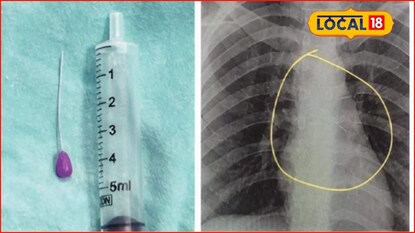

छत्रपती संभाजीनगर : घरगुती कामात सहज वापरली जाणारी एक छोटीशी पिन कधी जीवावर बेतू शकते, याचा थरारक अनुभव छत्रपती संभाजीनगरमध्ये आला. क्षणभराचा निष्काळजीपणा आणि अचानक आलेल्या ठसक्यामुळे 18 वर्षीय तरुणीच्या तोंडातील पिन थेट श्वसनलिकेत अडकली आणि तिच्या जीवावर बेतण्याची वेळ आली.

कपड्यांना पिन लावत असताना ती पिन तोंडात धरलेली असतानाच अचानक ठसका लागला. काही कळायच्या आत पिन गिळली गेली आणि ती थेट श्वासनलिकेत अडकली. ही घटना शुक्रवारी घडली. सुरुवातीला त्रास सहन करण्याचा प्रयत्न केला; मात्र शनिवारी श्वास घेण्यास त्रास, तीव्र वेदना आणि भीती वाढल्याने तरुणीला घाटी रुग्णालयात दाखल करण्यात आले.

रुग्णालयात करण्यात आलेल्या एक्स-रे तपासणीत पिन श्वासनलिकेत अडकल्याचे स्पष्ट झाले. घाटी रुग्णालयाचे अधिष्ठाता डॉ. शिवाजी सुक्रे यांच्या मार्गदर्शनाखाली कान-नाक-घसा विभागातील डॉ. शैलेश निकम यांनी ब्राँकोस्कोपीच्या माध्यमातून ही पिन अत्यंत काळजीपूर्वक बाहेर काढली. डॉक्टरांच्या तत्परतेमुळे तरुणीचा जीव वाचवण्यात यश आले.